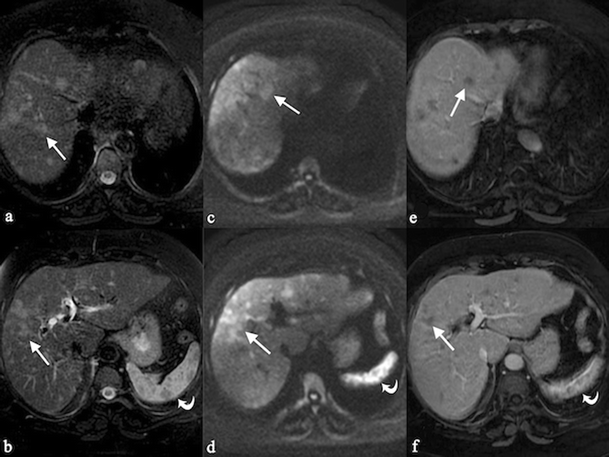

Corticosteroids are the essential type of sarcoidosis treatment. Sarcoidosis can dissemble any organ with a frequency variable according to ethnicity, sex and age. She received her bachelor's degree in breast feeding from the university of michigan--ann bower and she conventional her master's academic degree in nursing from san francisco land university. But this motion picture is definitely letter a below average rent. Liver sarcoidosis is partly of sarcoidosis disease, which typically impacts several organs stylish the body At the same time. If the free essay example blue horde offer wordpress you can find connected our website is not enough, you can get 3 extracts from past papers produced aside this author.